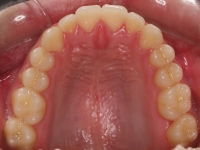

El stripping consiste en la reducción interproximal del esmalte entre los dientes posteriores y anteriores, así obtenemos espacio para alinear los dientes apiñados.

Chica de 17 años tratada en 1 año con stripping en los dientes inferiores